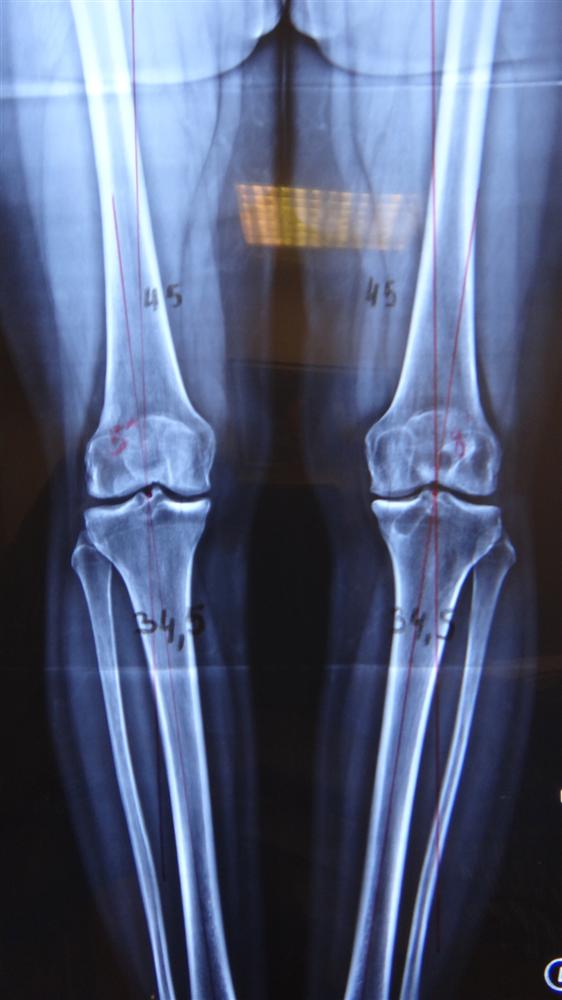

Knee Imaging Knee & Sports Orthobullets Sports Orthobullets Medial meniscus has less mobility with more rigid peripheral fixation than the lateral meniscus. Common activities are soccer, basketball, skiing, and football. Posterolateral corner (plc) injuries are traumatic knee injuries that are associated with lateral knee instability and usually present with a concomitant cruciate. Flex the knee and place a hand on medial side of knee, externally rotate the leg. Sports Orthobullets.